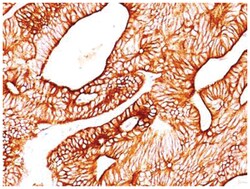

| Epitope of this MAb is located between aa343-357. Cytokeratin 8 (CK8) belongs to the type II (or B or basic) subfamily of high molecular weight cytokeratins and exists in combination with cytokeratin 18 (CK18). CK8 is primarily found in the non-squamous epithelia and is present in majority of adenocarcinomas and ductal carcinomas. It is absent in squamous cell carcinomas. Hepatocellular carcinomas are defined by the use of antibodies that recognize only cytokeratin 8 and 18. CK8 exists on several types of normal and neoplastic epithelia, including many ductal and glandular epithelia such as colon, stomach, small intestine, trachea, and esophagus as well as in transitional epithelium. Anti-CK8 does not react with skeletal muscle or nerve cells. Epithelioid sarcoma, chordoma, and adamantinoma show strong positivity corresponding to that of simple epithelia (with antibodies against CK8, CK18 and CK19). Reportedly, anti-CK8 is useful for the differentiation of lobular (ring-like, perinuclear) from ductal (peripheral-predominant) carcinoma of the breast. |